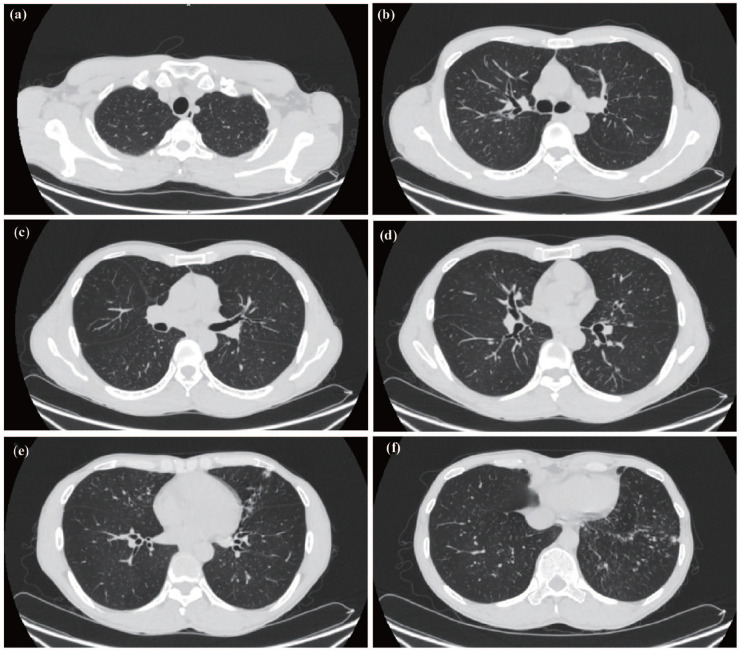

Tyrosine kinase 2 (TYK2) deficiency is a rare primary immunodeficiency disease (PID). Patients carry TYK2 gene mutations and suffer from recurrent infections by intracellular pathogens, including mycobacteria. Delayed diagnosis often hinders timely and effective treatment, resulting in poor prognosis. In this study, we report a newly discovered TYK2 deficiency patient with recurrent pulmonary infections. The patient, a 27-year-old Chinese man with a history of tuberculosis, presented with recurrent cough, phlegm, and purulent sputum. Lung CT scan showed bronchiectasis with concomitant infection. Next-generation sequencing (NGS) identified Mycobacterium gordonae and Mycobacterium chelonae in lung, along with heterozygous c.997G>A&c.10C>T (p.V333M&p.R4C) mutation in TYK2. Further pathogenicity prediction analysis via dbNSFP (v5.1a) suggested the potential pathogenicity of this genetic variant. Additionally, TYK2 mRNA expression in peripheral blood mononuclear cells (PBMCs) also decreased significantly. Following anti-infective treatment, the patient improved and was discharged with regular human immunoglobulin infusion. However, the patient unfortunately succumbed to disease exacerbation in October 2021, 15 months after diagnosis. Furthermore, a literature review was conducted on cases of TYK2 deficiency. Previous studies have identified 24 mutation sites within TYK2 gene, which impair immune function and lead to early-onset recurrent infections. These mutations contribute to clinical heterogeneity, with the most common manifestation being recurrent infections by opportunistic pathogens, particularly mycobacteria. Our discovery of a novel TYK2 mutation expands the gene's mutation spectrum. Analyzing the characteristics of reported cases enhances understanding of TYK2 deficiency's clinical manifestations and facilitates early diagnosis of this rare condition.